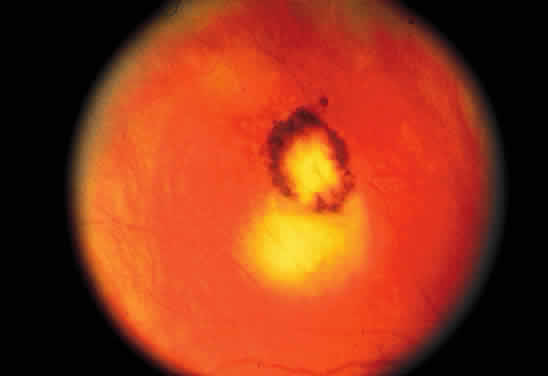

Bradyzoites are slowly metabolizing organisms found in cysts formed within the tissue of the infected host. The size of the Toxoplasma cyst varies, depending on the number of organisms that have multiplied within it. The cyst may reach more than 100 μm in diameter and may contain from 50 to 3000 organisms. The cyst wall is strongly argyrophilic and periodic acid-Schiff positive. It contains constituents that are derived from both the parasite and the host tissue. Constituent from the host tissue compose the outer part of the cyst, whereas those derived from the parasite are in the inner part of the cyst wall. Toxoplasmosis may be found in the inner layers of the retina after episodes of acute retinochoroiditis. The cyst may stay in the retinal tissue for years without showing any signs of invasiveness. Considering that the tissue cyst incorporates elements derived from the host into its outer wall, it is easily tolerated by the host, and no inflammatory reaction is seen around it (Fig. 2). It may remain for years in certain tissues, such as the eye or muscles, without provoking any inflammatory reactions. The bradyzoite inside the cyst derives its nutrition from the slow diffusion of substances through the cyst wall. The number of organisms increases within the cyst in the retina, and once the cyst wall breaks down by mechanical stretching, the bradyzoites escape, convert into tachyzoites, and invade contiguous cells. This process may lead to recurrence of retinitis. Certain immunologic mechanisms of the host may influence the organisms significantly. Immunosuppression coinciding with the rupture of the cyst and release of bradyzoites allows the organisms to become tachyzoites and proliferate in host tissue without restriction. The cyst of the Toxoplasma organism appears to be a defensive stage in its life cycle. The resistance of toxoplasmosis within chronically infected tissues of animals may lead to transmission of the disease by the ingestion of undercooked meat, including mutton, beef, pork, and chicken. Tissue cysts can develop within any organ and are commonly found in infected tissues of brain, eye, heart, skeletal muscles, and lymph nodes. Rupture of tissue cysts causes reactivation of the systemic toxoplasmosis in immune deficiency states, leading to dissemination of Toxoplasma organisms to other organs.